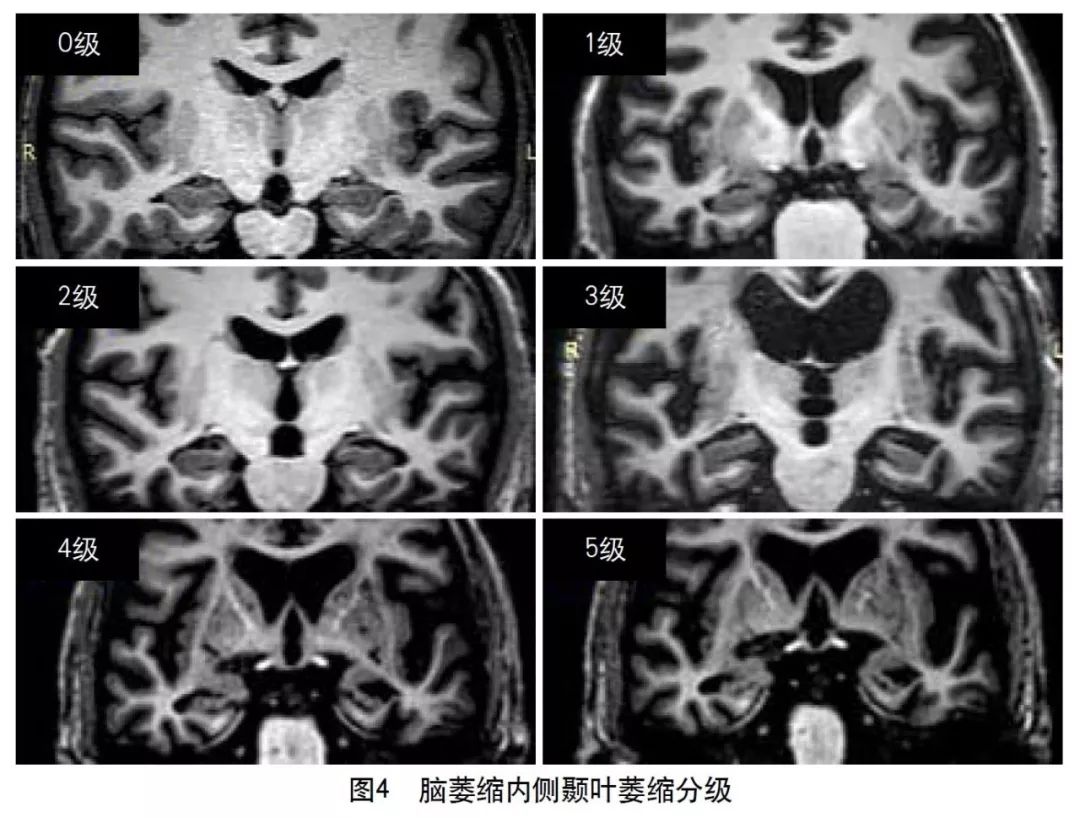

2013年的共识指南将脑萎缩定义为与特定的局灶性损伤,如脑外伤或脑梗死无关的脑容积减少。脑萎缩可以是广泛的或局部的(如特定的脑叶或海马等特定区域),可以是对称或不对称的,亦可以是组织选择性的(如发生在白质等某一特定组织层)。目前不同部位的脑萎缩有相应的诊断标准,全脑皮层萎缩分级用于评价全脑(图3);内侧颞叶萎缩分级主要评价颞叶内侧,重点是海马(图4);Koedam分级主要评价顶叶,尤其是扣带回和楔前叶(图5);Kipps/Davies分级主要评价额颞叶(图6)。推测脑组织减少是由脑沟(周围)和脑室(中心)的脑脊液空间相对于颅内容积扩大所引起的。